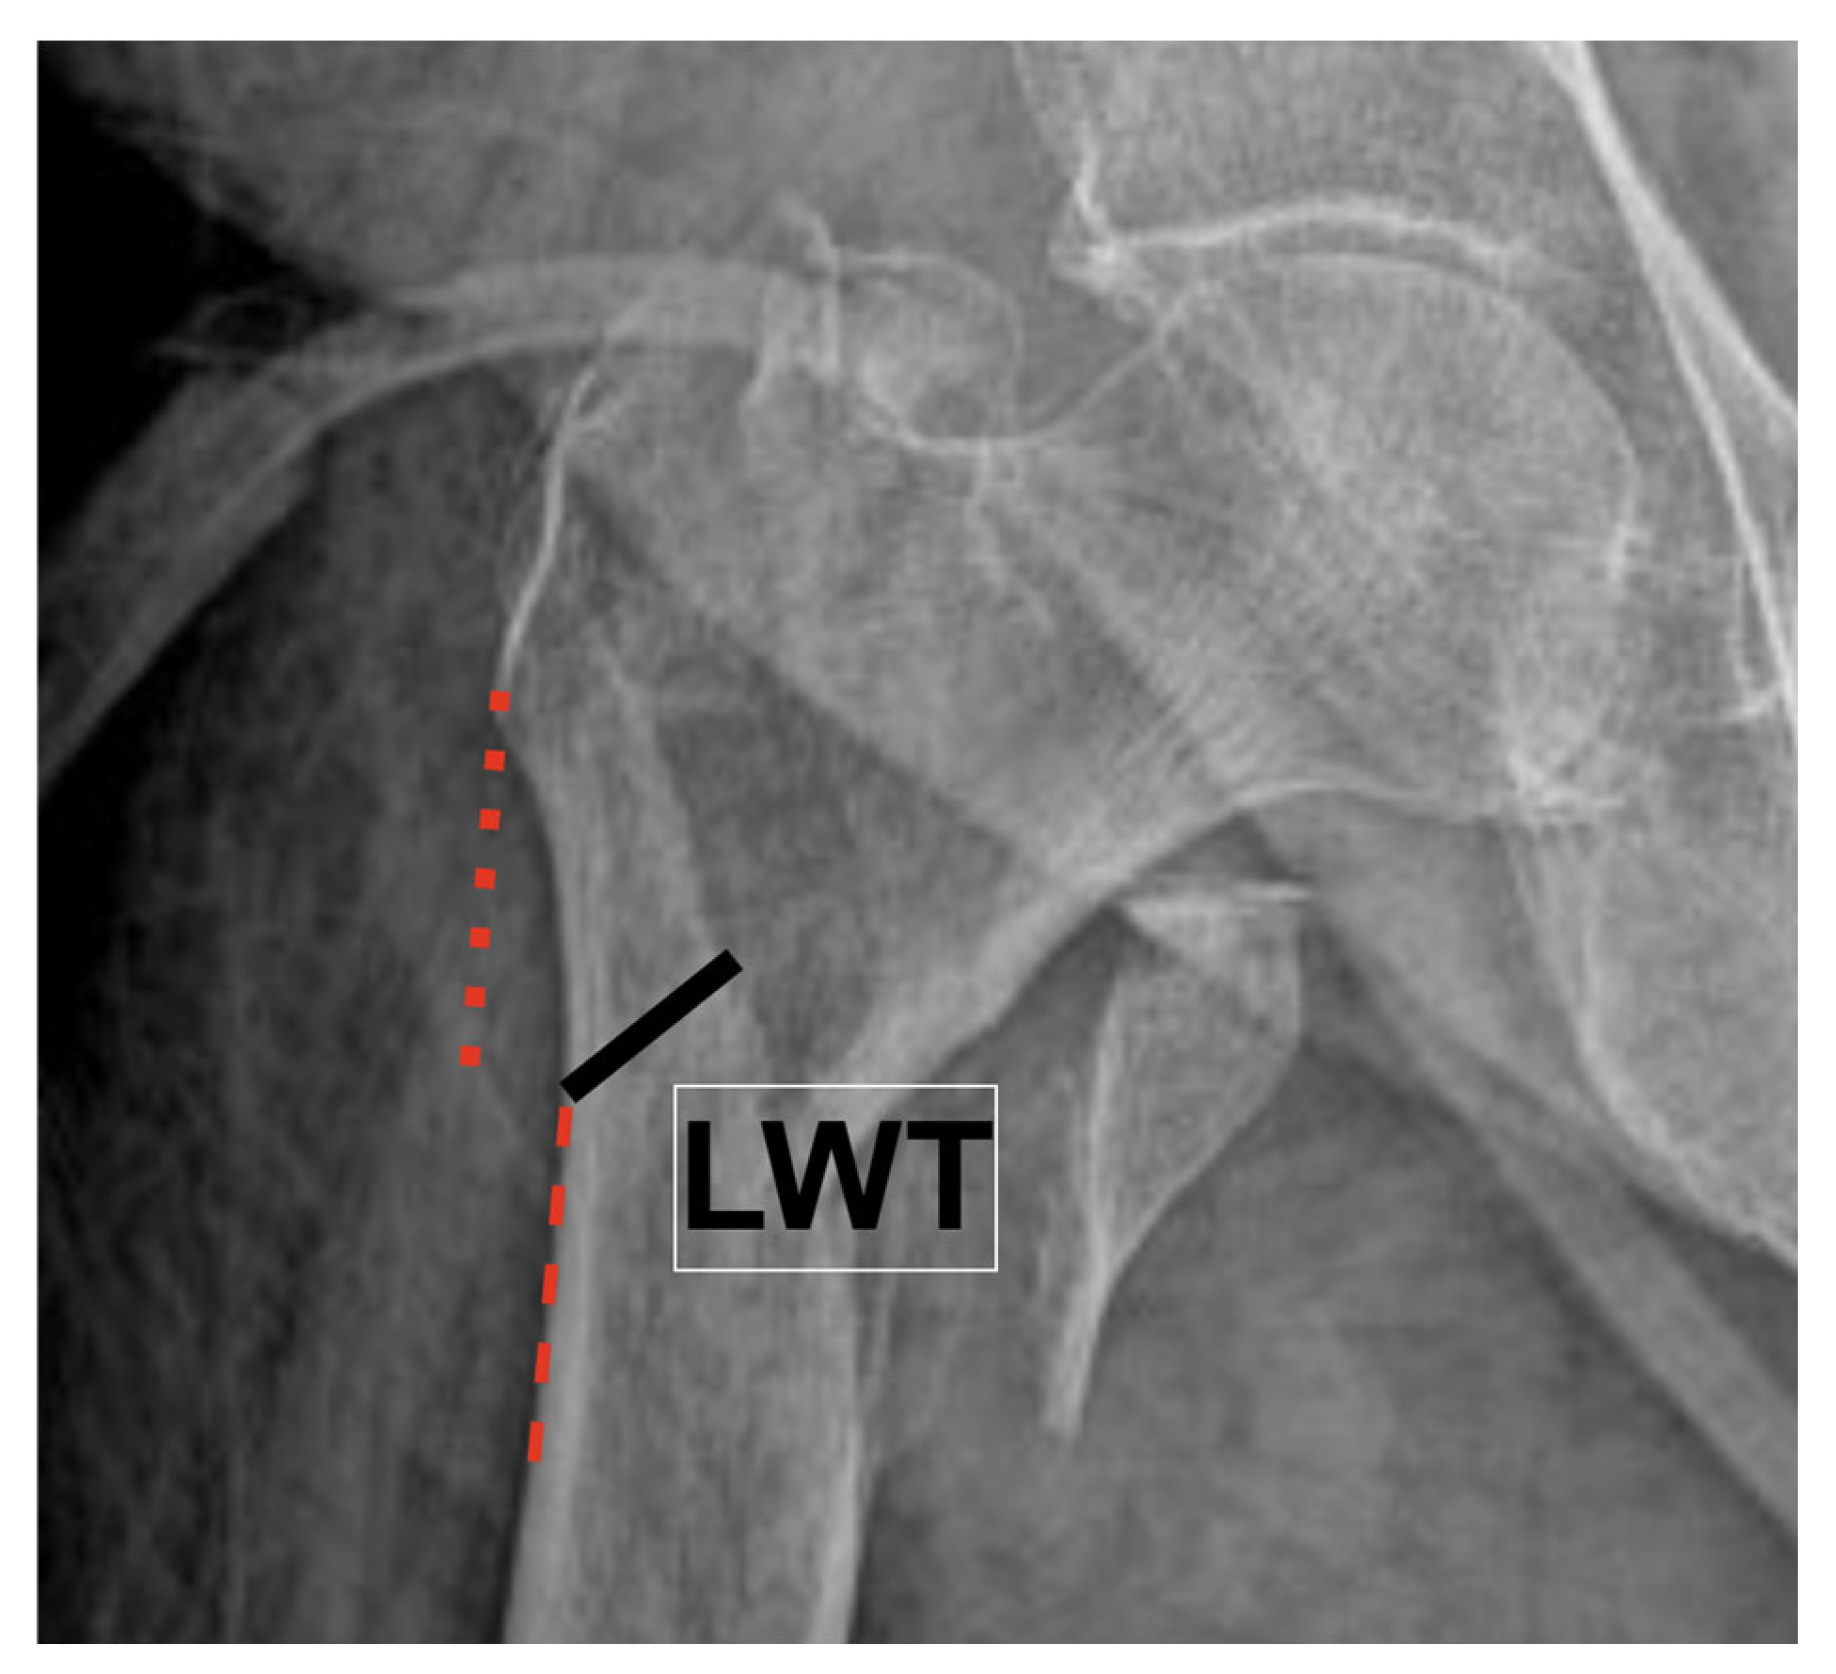

| LWT | Lateral Wall Thickness |

| Lateral wall thickness (mm) | 16.68 (12.3–22.32) [17.87 ± 7.66] | 16.98 (13.16–21.53) [17.55 ± 6.41] | 0.799 | 0.99 (0.95–1.04) |